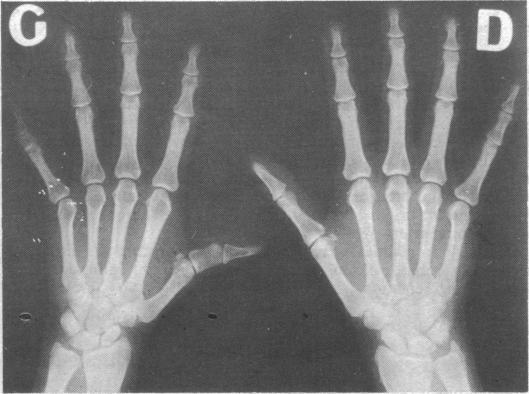

Subtyping of hepatitis B antigen (HBA) in blood donors revealed subtype ad in 56% while patients with icteric post-transfusion hepatitis from the same centre showed subtype ay in the majority of the cases (75%). Donors with subtype ad in serum were mostly asymptomatic long-term carriers of the antigen with normal liver function (83%), while 70% of donors with subtype ay in serum had signs of acute or chronic liver disease. Healthy long-term carriers of HBA seem to present little risk of transmitting hepatitis irrespective of subtype. It is, however, possible that these differences in blood donors with subtype ad and patients with post-transfusion hepatitis with subtype ay might reflect epidemiological circumstances rather than biological differences in the two viral strains.

对献血者的乙肝抗原(HBA)进行亚型分型显示,56%为ad亚型,而来自同一中心的输血后黄疸型肝炎患者大多数病例(75%)为ay亚型。血清中为ad亚型的献血者大多是肝功能正常的无症状长期抗原携带者(83%),而血清中为ay亚型的献血者70%有急慢性肝病迹象。无论亚型如何,健康的HBA长期携带者似乎传播肝炎的风险很小。然而,血清中为ad亚型的献血者与输血后肝炎患者中为ay亚型的这些差异可能反映的是流行病学情况,而非两种病毒株的生物学差异。